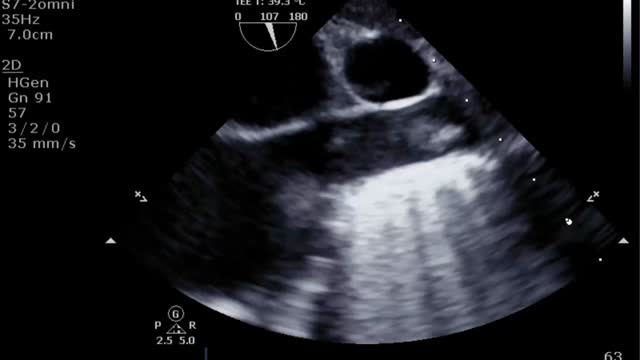

El destete supone un proceso de descenso gradual (500ml cada 15-20min) del soporte de la ECMO VA de manera que se restablece progresivamente la precarga en el corazón. Para ello el paciente debe estar adecuadamente anticoagulado. Evaluaremos la repercusión hemodinámica (PVC, PAM y diferencial, SvO2, SatO2) y ecocardiográfica (FEVI, IVT, onda E, onda E’ o S’ del anillo mitral lateral) que tiene hasta un nivel (normalmente 1-1,5l/min) que nos indique que el paciente puede tolerar la retirada de la asistencia. Durante esta, evaluaremos que mantiene e incluso aumenta la FEVI por encima del 25-30%, la IVT por encima de 10cm y la onda S’ de más de 6cm/s (fig. 5 y suplementario 22). Junto con ello, también evaluaremos el comportamiento de las cavidades derechas (desplazamiento sistólico del plano del anillo tricuspídeo>16cm, S’>10cm/s y tamaño VD) y la posible aparición de signos de hipertensión pulmonar (aumento de la velocidad pico de la insuficiencia tricuspídea) que predigan un fracaso de VD38–40.

Evaluación ecocardiográfica de destete de paciente con ECMO VA. Ecografía transtorácica e integral velocidad-tiempo (IVT) del tracto de salida del ventrículo izquierdo al reducir flujo (A: 3L/min, B: 2,5L/min, C: 2L/min) de ECMO VA. Obsérvese el aumento del tamaño de la IVT y consecuentemente del volumen sistólico y del gasto cardiaco.